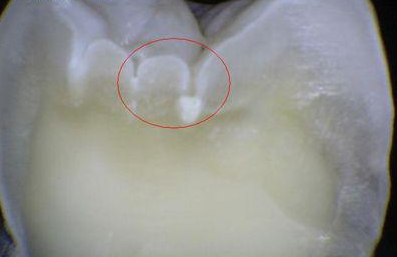

2. CÓDIGO 5

1. Cavidad visiblemente detectable con paredes en esmalte y piso en dentina.

1. DIAGNOSTICO DENTAL: CARIES CAVITACIONAL (ACTIVA / NO ACTIVA). Es activa cuando a la exploración clínica con cucharilla el tejido cariado se puede retirar acompañada de otros signos como encía enrojecida y presencia de sangrado, cuando es inactiva vemos que hay dentina reparativa de por medio, esta se ve opaca y no brillante.

1. TRATAMIENTO: Orientación en normas y educación de higiene oral al padre/madre/menor, control de placa, profilaxis, si esta lesión llega a afectar algún cuerno pulpar se debe de realizar una pulpotomía junto con una restauración ya sea en amalgama o composite, si esta lesión no es tan severa se retira la caries posterior a esto se realiza la reconstrucción de la pieza dental. Aplicación de barniz fluorado.